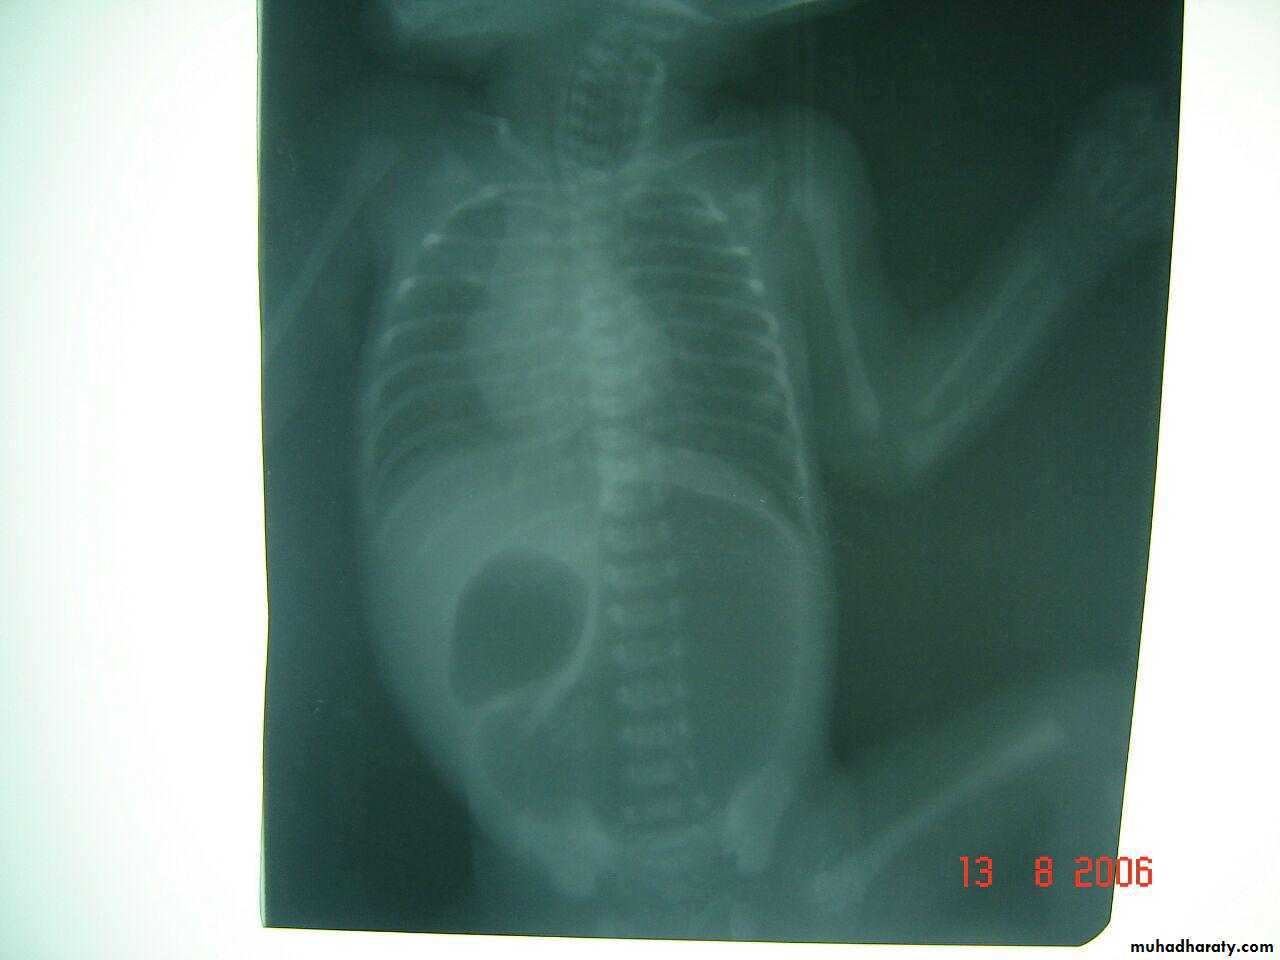

Deudenal obstruction double bubble sign

Rx iv fluid , surgeryDouble bubble sign deudenal obstruction + air fluid level

3 bubble apperance of jujenal atresia

Double bubble apperance of dudenal atresia